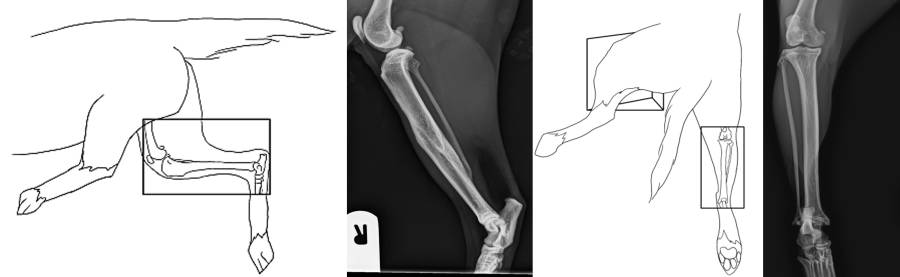

Röntgen Ellbogen

Röntgen Tarsus

Röntgen prä-OP TPLO